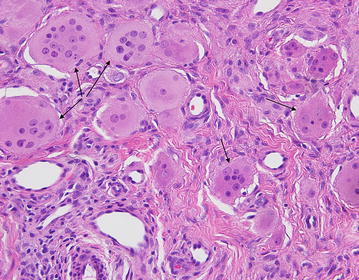

Initial clinical differential diagnosis included dermatomyositis, rheumatoid arthritis, and psoriatic arthritis. A skin biopsy demonstrated numerous multinucleated histiocytes infiltrating between the collagen bundles in the superficial dermis (Fig. 3). There is a Grenz zone separating the epidermis from the dermal tumor. The multinucleated histiocytes are large with an eosinophilic and finely granular “ground-glass” cytoplasm. The nuclei are haphazardly arranged, but tend to favor the center of the cells (Fig. 4). Additionally, there are an increased number of blood vessels amongst the histiocytes, as well as scattered lymphocytes. A CD163 stain was diffusely positive and the cells were focally PAS-positive diastase-resistant. The cells were negative for S100. Polarization did not reveal and polarizable material. These findings are diagnostic of MRH.

Fig. 4.

The multinucleated histiocytes (arrows) are large with an eosinophilic and finely granular “ground-glass” cytoplasm. The nuclei are haphazardly arranged, but tend to favor the center of the cells. A CD163 stain was diffusely positive and the cells were focally PAS-positive diastase-resistant